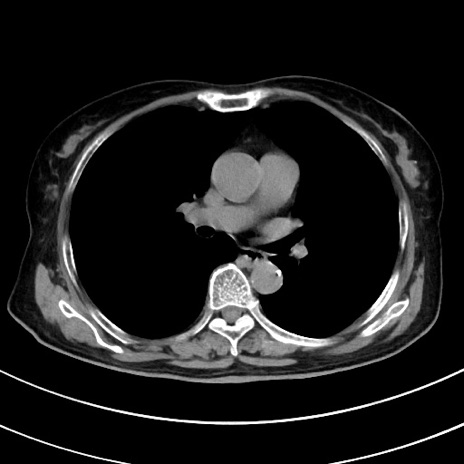

症例33(横断像)

【症例】70歳代 女性

【主訴】心窩部痛

【現病歴】延髄病変の精査・加療にて神経内科入院中。本日より心窩部痛あり。

【既往歴】虫垂炎

【身体所見】右下腹部を中心に圧痛と反跳痛あり。

【データ】WBC 10900、CRP 0.02